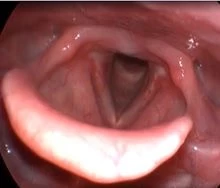

Клинический случай №1. Удаление папилломы правой голосовой складки с использованием СО2-лазера.

После процедуры проявления воспаления в области голосовой складки были практически незаметны.

Рис 1А. Папиллома правой голосовой складки. До операции.

Рис 1Б. Папиллома правой голосовой складки. На 1 сутки после операции.

Рис 1В. Папиллома правой голосовой складки. На 7 сутки после операции.